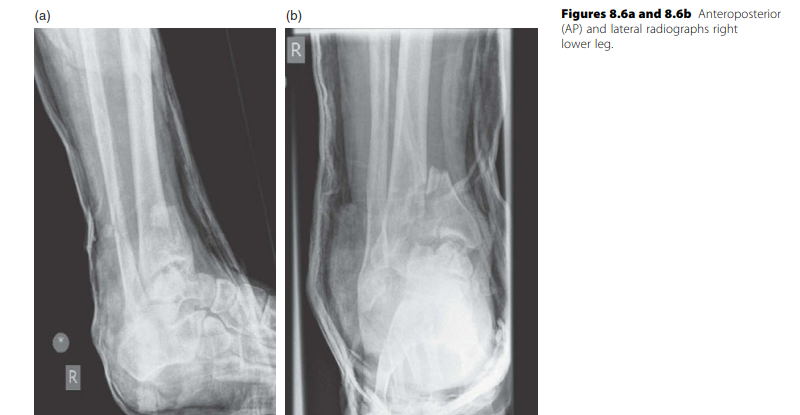

Lower limb Trauma Structured oral examination question 3 Minutes 1 and 2 EXAMINER : A 49-year-old lady fell o…